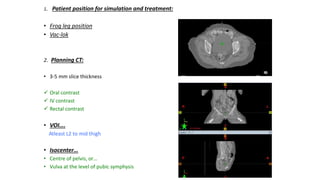

1. Patient position for simulation and treatment:

• Frog leg position

• Vac-lok

2. Planning CT:

• 3-5 mm slice thickness

 Oral contrast

 IV contrast

 Rectal contrast

• VOI….

Atleast L2 to mid thigh

• Isocenter…

• Centre of pelvis, or…

• Vulva at the level of pubic symphysis